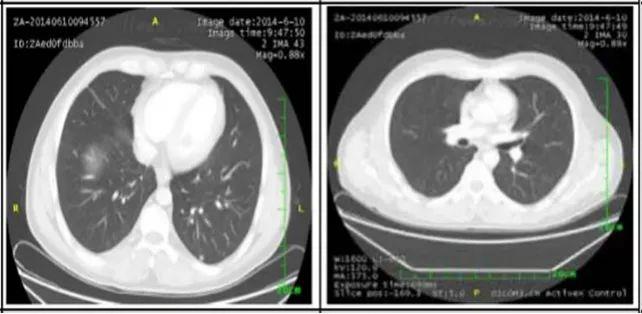

2. 肺部病灶治疗前后核磁对比:

肺部转移病灶在用药后2个月明显缩小,4个月后病灶基本消失。

治疗6个月

治疗16个月